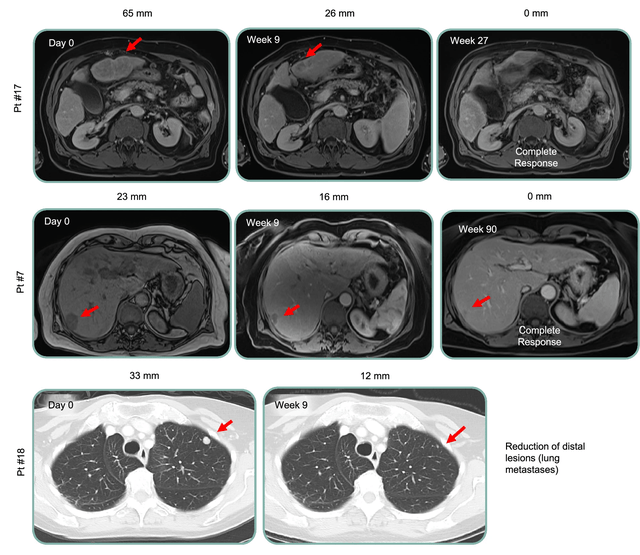

患者11在接受联合治疗后,肝脏肿瘤持续缩小-第18周时肿瘤缩小59%,表明治疗可能带来长期获益。

其他代表性临床反应如下: